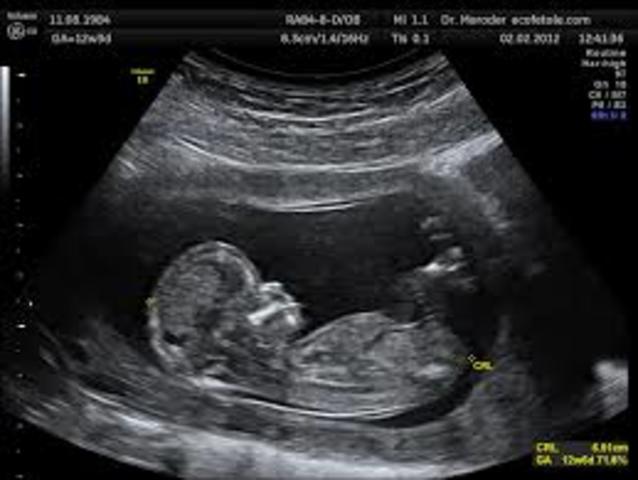

• period of fetus

period of fetus

week 9, the fetus is an inch long. The size of a grape. Baby's heart finishes dividing into four chambers, also teeth star developing. Eyes are formed and positioned to rapid weigh gain.